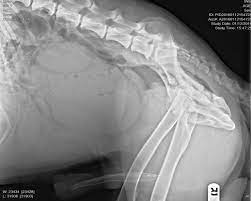

Dogs over 8 years are prone to develop prostate cancer. Hemivertebrae are congenitally deformed vertebra in dogs and cats. Prostate cancer has similar symptoms to other types of prostate disease. The rear legs look stiff and the dog takes very small steps. As a matter of fact, prostate disease affects 60% of male dogs over five and close to 95% of male dogs before they are 10 years old.

According to the dog cancer news dated mar.20,2020, castration of dogs increases total malignant prostate cancer by eight times. There is one prostatic disease which is not prevented by neutering. Intact dogs are prone to infection which can't be cleared without neutering. In many cases, a dog will show signs of these problems on average by the age of 8: Protruding vaginal masses in dogs. In the dog cancer survival guide, dr. Due to the enlargement of the prostate gland, it may push itself up against the wall of the urethra. Hemivertebrae are congenitally deformed vertebra in dogs and cats. It is seven months old. Other possible symptoms include pain, weight loss, fever and lethargy. As one of the species to have a prostate, an intact male dog shows a higher risk for prostate problems the older he gets. Cancer unlike in men, prostate cancer is not common in male dogs. If the prostate is very enlarged, the colon, located just above the prostate, may also become compressed, causing difficulty with passing bowel movements.

Prostatic adenocarcinoma is seen in both intact and neutered dogs, representing about one percent of all malignant tumors found in dogs. When the prostate gland becomes enlarged it presses against the wall of the urethra (the tube which connects the bladder to the outside of the dog), making it very difficult for your dog to urinate. Hemivertebrae are congenitally deformed vertebra in dogs and cats. Therefore, prostate cancer is more commonly seen in castrated. These symptoms are all associated with prostate disease;

Prostate disease is an enlarged prostate gland and it is the number one disorder seen in male dogs that have not been neutered. It is frequently seen after the age of 5, and sometimes. As a matter of fact, prostate disease affects 60% of male dogs over five and close to 95% of male dogs before they are 10 years old. As one of the species to have a prostate, an intact male dog shows a higher risk for prostate problems the older he gets. Canine prostate cancer can affect dogs that are neutered or unneutered (intact), so if you have a male dog, it's good to keep an eye out for any symptoms! Happily, the majority of dogs respond well to therapy once they show signs and a diagnosis made. Other possible symptoms include pain, weight loss, fever and lethargy. When it does happen, this cancer can metastasize (or spread) to other organs such as the liver or lymph nodes. Some dogs have blood in their urine. The most common type is carcinoma (e.g. Benign prostatic hypertrophy or hyperplasia, aka bph: General pain, overall debilitation and weakness, decreased appetite and weight loss. Hemangiosarcoma is blood or skin cancer in dogs and cats.

Normal joints look like this in dogs and cats. There are various types of canine prostate cancer. A study carried out in 2002 (4) showed that castration does not cause prostate cancer but it may favour tumour progression. Therefore, prostate cancer is more commonly seen in castrated. Prostatic adenocarcinoma is seen in both intact and neutered dogs, representing about one percent of all malignant tumors found in dogs.

It is seven months old. According to the dog cancer news dated mar.20,2020, castration of dogs increases total malignant prostate cancer by eight times. Due to the enlargement of the prostate gland, it may push itself up against the wall of the urethra. Dogs experience discomfort as the prostate enlarges and puts pressure on the urethra, making it difficult for the dog to both urinate and defecate. As the dog's prostate enlargement progresses the prostate pushes itself against the urethra's wall. It appears that canine prostate cancer arises with similar frequency in neutered and intact male dogs. Symptoms of prostate cancer in dogs canine prostate cancer has various signs and symptoms and can resemble those of an enlarged prostate. The rear legs look stiff and the dog takes very small steps. The glandular tissue of the prostate grows in size with age and puts pressure on surrounding areas (e.g. While we can't identify a specific cause, we know that there are both environmental and genetic factors that cause prostate cancer in dogs, and there. For example, some pets may exhibit lethargic behavior or. As a matter of fact, prostate disease affects 60% of male dogs over five and close to 95% of male dogs before they are 10 years old. Prostate cancer has similar symptoms to other types of prostate disease.